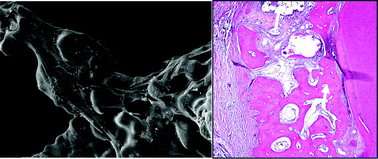

Bioactive scaffolds play an important role in periodontal tissue engineering. Nagelschmidtite (NAGEL:Ca7P2Si2O16) is a newly synthesized bioceramic which can stimulate the proliferation and osteogenic/cementogenic differentiation of periodontal ligament cells (PDLCs) for potential periodontal regeneration. The aim of this study is to prepare porous NAGEL scaffolds and to systematically investigate their in vitro and in vivo osteogenesis/cementogenesis. The NAGEL scaffold with highly porous structure and large pores was successfully prepared by a spongy-templated method. The interaction of the NAGEL scaffold with PDLCs was studied by investigating cell attachment, proliferation and osteogenic differentiation of PDLCs. NAGEL scaffolds were implanted into the periodontal defects of beagle dogs to evaluate their in vivo osteogenesis/cementogenesis. The results showed that NAGEL scaffolds supported the attachment and proliferation of PDLCs, and significantly enhanced osteogenesis/cementogenesis-related gene expression of PDLCs, compared to β-TCP scaffolds. The in vivo study showed that the rate of new bone formation in NAGEL scaffolds was higher than that in conventional β-TCP scaffolds, which was evidenced by the significantly improved BSP and OPN expression at both 4 and 8 weeks. The results suggested that NAGEL scaffolds could be used for periodontal tissue engineering with significantly improved in vitro and in vivo osteogenesis/cementogenesis.